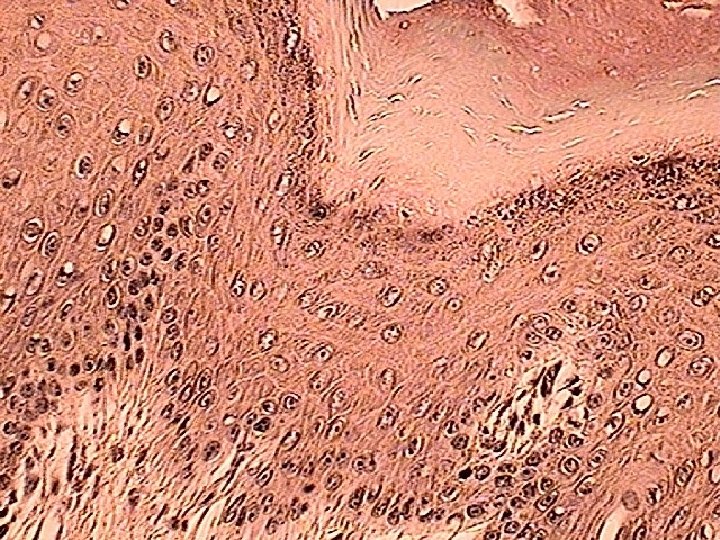

Specific Layers of the Epidermis Stratum Basale: • Mitotic layer, continuously replaces epidermal cells, turnover rate between 25 to 50 days Stratum Spinosum: • Cells are pushed upward and flatten out Stratum Granulosum: • Cells contain granules of Keratin

Specific Layer of the Epidermis Stratum Lucidum: • Observed only in nonhairy or thick skin. Several layers of dead cells with indistinct boundaries Stratum Corneum: • Composed of 25 or more layers of dead squamous cells still joined by desmosomes. Eventually desmosomes break and cells flake off in a process called desquamation

Growth of the epidermis • Takes between 25 – 50 days for a keratinocyte to move from stratum basale to the surface • We shed 30 – 40, 000 skin cells a day, 8 lbs a year!!

Specialized Cells of the Epidermis Keratinocytes: Most common cells of the epidermis. Provides protection and waterproofing sealant Melanocytes: Produces and transfer the protein melanin to Keratinocytes. Melanin is a brown/black pigment that absorbs UV-light.